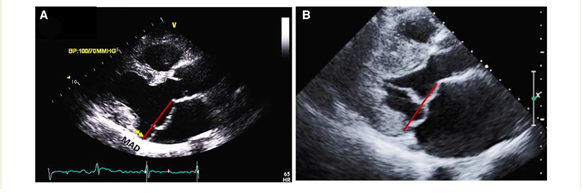

Furthermore, MVP can be associated with mitral annulus disjunction (MAD), which involves the separation between the ventricular myocardium and the mitral annulus during systole, particularly occurring beneath the posterior leaflet scallops but primarily at the central posterior one. MAD is associated with the loss of normal mechanical annular function due to its detachment from the ventricular myocardium while maintaining its electrical function, thereby isolating the left atrium and ventricle electrically. Although it is typically observed in conjunction with MVP, it can occur independently (2).

The presence of MAD should be detected as well. It may manifest at various locations on the mitral annulus, but it carries an increased risk of VAs when observed at the posterior LV wall. Occasionally, MAD is associated with a distinct mid-systolic to late-systolic spike on the lateral mitral annulus, as detected by Doppler. To measure MAD's length, the parasternal long-axis view at end-systole is employed, defining it as the distance between the mitral annulus and the systolic bulge of the ventricular myocardium (typically ranging from 5–10 mm in long-axis view) (5,6).